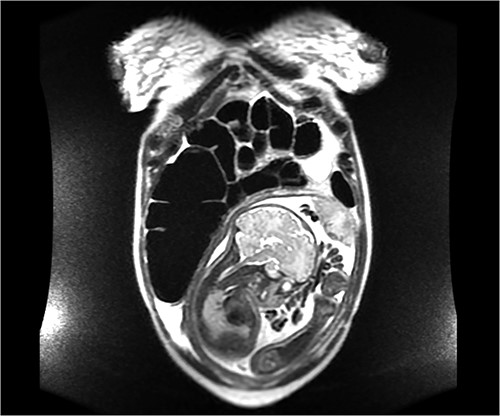

On hospital day 2, the patient became obstipated, and her abdominal exam had notable distension with persistent right upper quadrant tenderness. An abdominal magnetic resonance imaging (MRI) was performed revealing dilated small intestine with air-fluid levels and an inverted-appearing, prominent cecum (Figs. 1 and 2). The patient was diagnosed with an acute abdomen from probable cecal volvulus versus appendicitis and was urgently taken to the operating room for cesarean section (c-section) to facilitate abdominal exploration. After delivery of the child, a cecal bascule was found, with a severely distended cecum (Fig. 3). Because the cecum and ascending colon were deserosalized, a right hemicolectomy with primary ileocolic anastomosis was performed. The patient had return of bowel function on post operative day 5 and was discharged home on day 7.

Axial image of an abdominal MRI on a 36-week pregnant patient with a dilated cecum anteriorly displaced to the ascending colon. Arrows mark the point of inflection.